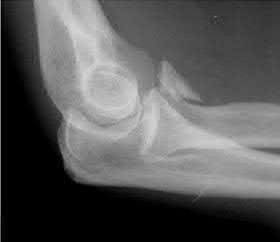

A 26-year-old male sustains an elbow injury after a fall from a skateboard resulting in valgus and supination forces across the left elbow. A CT scan of the left elbow is shown in Figures A through D. This fracture pattern is most commonly associated with what other traumatic elbow pathology?

The clinical presentation is consistent with a coronoid tip fracture. This fracture pattern is associated with a radial head fracture and posterolateral ulnohumeral dislocation - together making up the terrible triad injury.

A terrible triad injury is the result of a valgus and supination injury and involves posterolateral elbow dislocation or lateral collateral ligament injury, radial head fracture, and fracture of the coronoid process. The elbow may dislocate postero-laterally with the anterior bundle of the MCL intact, but if the MCL is injured it is typically the last structure to fail. The coronoid fracture is typically a small fragment isolated to the tip. This is a result of a posteriorly directed force driving the coronoid into the trochlea prior to posterior elbow dislocation. CT scan is a useful modality when small or comminuted fragments are difficult to visualize on plain radiographs.

Figures A through D show consecutive 2.00 mm sagittal CT reformats demonstrating a small coronoid fracture fragment which was addressed with suture fixation.